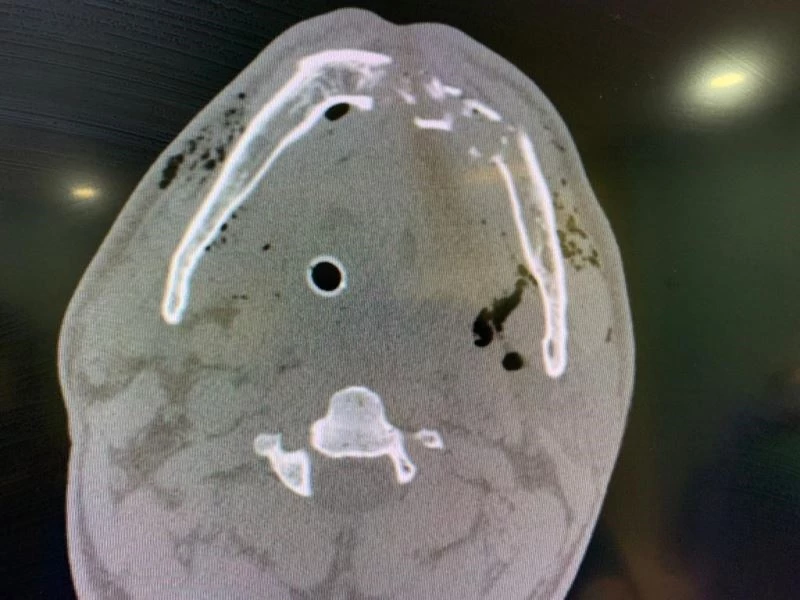

Hastayı tekrar yaşama döndüren SBÜ Ankara Atatürk Sanatoryum Eğitim ve Araştırma Hastanesi Kulak Burun Boğaz Kliniği Eğitim ve İdari Sorumlusu Prof. Dr. Aydın Acar ise yaptığı açıklamada, "Hastamız 48 yaşında erkek hasta. Nisan ayının 12’sinde ateşli silah yaralanması sebebiyle başka bir hastaneden buraya sevk ile getirildi. Hasta nefes alamıyordu. Hastanemize gelir gelmez gerekli müdahaleleri yaptık, 24 Nisan’da ameliyata aldık. Ameliyatta alt çene dediğimiz mandibula kemiğinde kırıklar vardı. Biz bu alana cerrahi olarak hem mini plaklar hem normal plaklarla beraber kemik onarımı yaptık. Sonrasında hastaya nefes borusundan delikler açarak rahat nefes almasını sağladık. Yaklaşık bir haftalık dönemden sonra nefes borusundaki deliği kapattık ve normal takibe devam ettik. Şu anda yaklaşık ikinci haftamız. Yeme içmesi de düzene girdi. İnşallah bugün de taburcu edeceğiz" ifadelerini kullandı.

Prof. Dr. Aydın Acar, ameliyat süreci ile ilgili şu bilgileri verdi:

"Silahlı yaralanmayla gelen hastada mermi bulamadık. Mermi kafaya ve özellikle alt çenede tahribat vererek terk etmişti. Mevcut lezyon yerindeki parçada kırıklar oluşturmuştu. Bu kırıklarla beraber doku kaybı vardı. Biz hem o kırıkları onarımla beraber mevcut doku kayıplarını yine hastadan tamamlayarak tedavi planına gittik. Hastamız geldiğinde birkaç günlük yoğun bakım süreci yaşadı. Orada gerekli müdahaleleri yaparak takip ettik. Sonrasında ameliyat daha sonrasında da servisimizde takip ettik. Hastanın yeme, içme ve gerekli diğer şeyleri planladıktan sonra bugün itibarı ile taburcu ediyoruz. Taburcu ederken de dikkat etmesi gereken durumlar hakkında gerekli uyarı ve önerilerimizi yaptık."